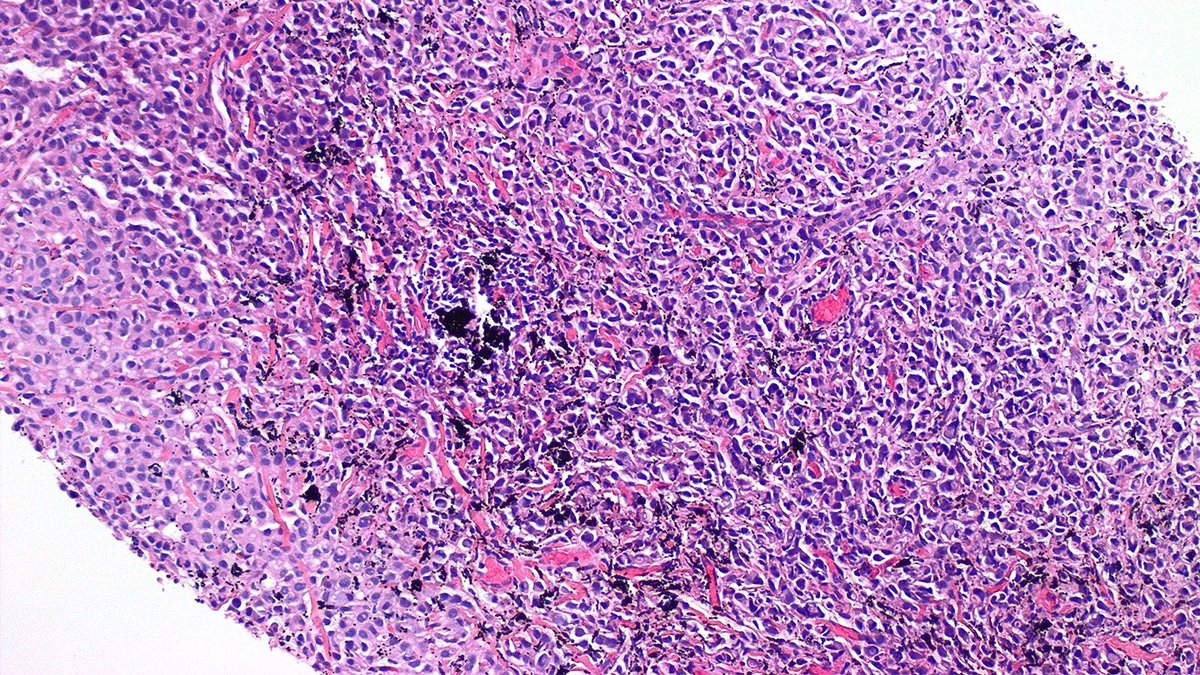

Case of Metastatic Carcinoma and Tattoo Pigment 🔬 Never stop looking once you’ve identified one finding! In this nodal biopsy, tattoo pigment from the patient’s arm is eye-catching, but metastatic lobular carcinoma lurking in the background. #PathX #PathTwitter #breastpath

Case of Metastatic Carcinoma and Tattoo Pigment 🔬

Never stop looking once you’ve identified one finding! In this nodal biopsy, tattoo pigment from the patient’s arm is eye-catching, but metastatic lobular carcinoma lurking in the background.